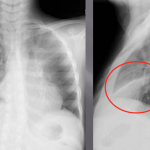

RIGHT LOWER LOBE ATELECTASIS

The archive below organizes different examples of a right lower lobe atelectasis. It will really be the anatomical location of the finding that will help diagnosis this SPECIFIC subtype of atelectasis.Whats more, this type of atelectasis often obscures the border of the right diaphragm. Click on the thumbnails below to view the archive.